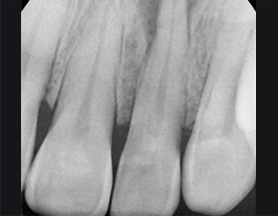

치근단 부위 회복

염증을 제거하는 신경치료 후 치근단 부위가 빠르게 회복되어 깔끔하게 신경치료를 완료하고 크라운 보철물을 씌웠습니다.